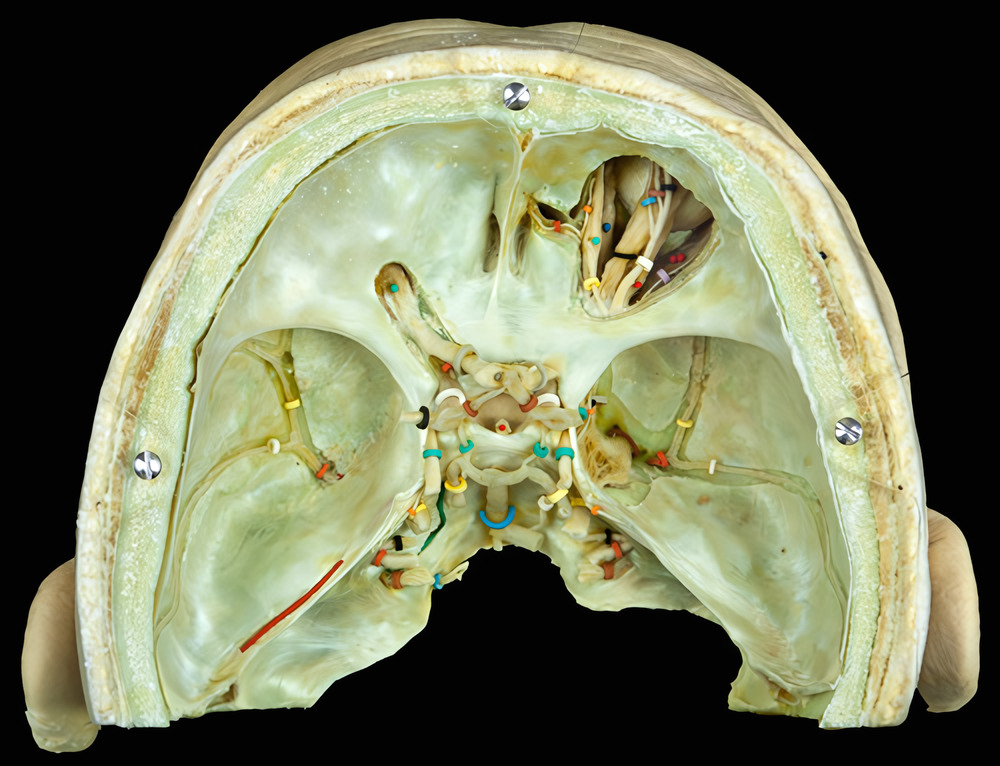

Aa-1-33 / 33-14

Skab 33

Præparatets øvre flade.

Orbita dxt.

m. levator palpebrae sup. (sort bøjle)

m. rectus sup. (rødt mærke)

m. rectus lat. (2 røde mærker)

m. rectus med. (blåt mærke)

m. obliquus sup. (grønt mærke)

n. frontalis (hvid ring)

n. supratrochlearis (blå ring)

r. frontalis (brun ring)

n. supraorbitalis (sort ring)

n. lacrimalis (grå ring)

n. trochlearis (gul ring)

n. ethmoidalis ant. (rød ring)

n. infratrochlearis (orange ring)

gl. lacrimalis (rødt mærke)

Orbita sin.

m. levator palpebrae sup. (grønt mærke)

bemærk anulus tendineus

I cavitas cranii ses:

n. opticus (grå ring)

n. oculomotorius (grøn ring)

n. trochlearis (orange ring)

n. trigeminus (gul ring)

n. abducens (hvid ring)

n. facialis (sort ring)

n. vestibulo-cochlearis (rød ring)

vagusgruppen (brun ring)

n. hypoglossus sin. (blå ring)

chiasma opticum (knappenål)

infundibulum hypofyseos (rødt mærke)

a. basilaris (blå ring)

a. cerebri post. (gul ring)

a. communicans post. (grøn ring)

a. cerebri med. (sort ring)

a. cerebri ant. (orange ring)

a. carotis int. (hvid ring)

a. ophthalmica sin. (rød ring)

a. meningea media (rød ring)

r. ant. (gul ring)

r. post. (hvid ring)

sinus petrosus sup. (rød sonde)

sinus petrosus inf. (grøn sonde)

n. mandibularis (brun ring)

bemærk ggl. trigeminale

Sinus cavernosus.

n. ophthalmicus (sort ring)

n. maxillaris (grå ring)